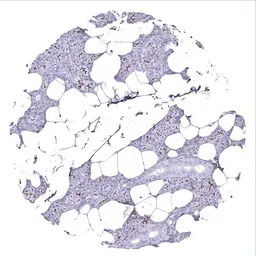

IHC-P analysis of human seminal vesicle tissue section using GTX04369 TMEM16A antibody [MSVA-201M] HistoMAX.